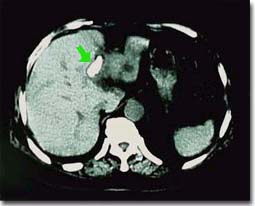

肝内胆管妇科好发于哪些部位?肝内胆管妇科可广泛分布于两叶胆管各分支内,亦可局限于一处,一般以左肝外叶或右肝后叶最为多见,可能与该处胆管弯度较大和胆汁引流不畅等有关。我国肝内胆管妇科大多数是原发性胆管妇科,其性质以胆色素钙妇科为主。肝内胆管妇科多数合并有肝外胆管妇科。

肝内胆管妇科的发病部位在急性期时,可出现急性化脓性胆管炎的症状,或不同程度的Charcot三联征,多数可能是合并的肝外胆管妇科所造成。在无合并肝外胆管妇科的病人,当一侧或一叶的肝内胆管妇科造成半肝或某一肝段的肝内胆管梗阻,并继发感染时,可出现畏寒、发热等全身感染症状,甚至在出现精神症状和休克等急性重症胆管炎的表现时,病人仍可明显的腹痛和黄疸.体检可扪及肝脏不对称性肿大和压痛,常易误诊为肝脓肿或肝炎。